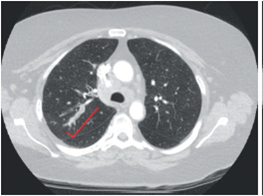

As shown in figure 1, computed tomography of the chest revealed a 3 x 1 cm mass in the posterior bronchus of the right upper lung and rightsided paratracheal and supraclavicular adenopathies. Lymph node biopsy demonstrated a nonhematopoietic malignant neoplasm with strong expression of CD56, consistent with small cell neuroendocrine carcinoma.

Figure 1. Computed tomography of the chest showing the mass in the right upper lung